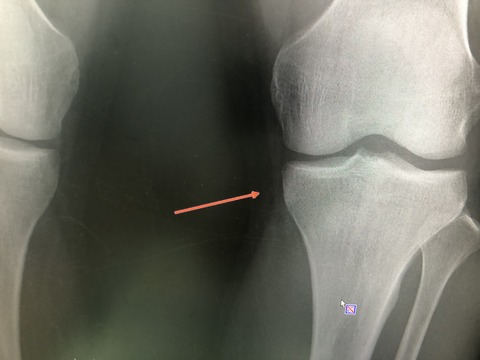

チームドクターしている

社会人野球選手 クロスプレーで受傷

骨の打撲で負傷  骨挫傷を起こし

筋肉をほぐし、テーピング、立体動態波で

早期復帰を目指す